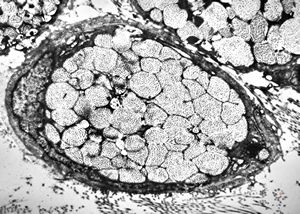

F, 1m. | sepsis - mycotic dermal lesions